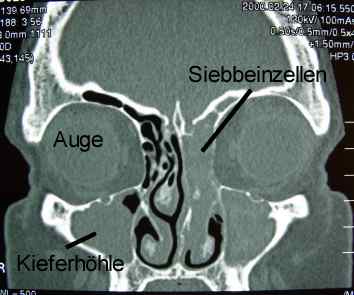

Chronische Sinusitis der Kieferhöhlen und des Siebbeines (Computertomografie)